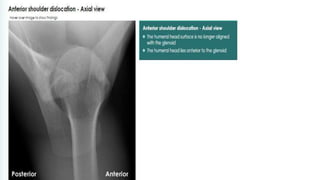

• An Axillary view is essential; it shows posterior subluxation

or dislocation and sometimes a deep indentation on the

anterior aspect of the humeral head.